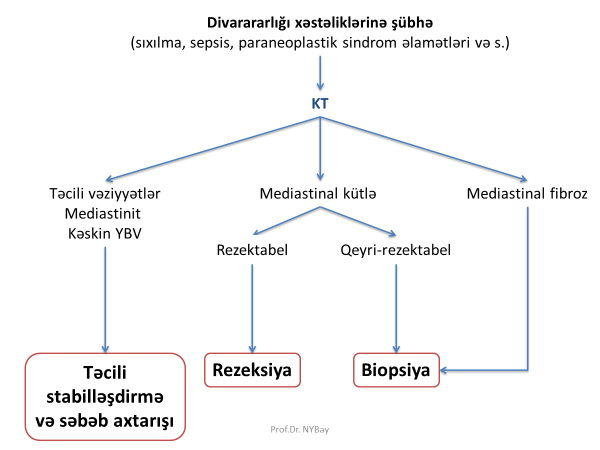

Diaqnostikası

Prinsipi

Kəskin mediastinit təcili müalicə tələb edən xəstəlikdir, ona görə də cüzi şübhə əlamətləri yaranan xəstələrdə təcili olaraq diaqnoz təsdiq və ya inkar edilməli, sonra isə səbəb müəyyənləşdirilməlidir.

Dəqiqləşdirmə

Kəskin mediastinitin diaqnozunu dəqiqləşdimək üçün ən vacib müayinə KT-dir. KT-də divararalığında ödem, maye, hava, kontrast ekstravazasiyası mediastinitin xarakterik əlamətləridir.

Səbəbin təyini

Müalicəsi

Prinsipi

Digər irinli iltihabı xəstələliklərdə olduğu kimi kəskin mediastinitin də müalicəsi “təcili 4 prinsip“ üzərində qurulur:

Cərrahi müalicə

Kəskin mediastinit şübhəsi olan xəstə təcili xəstəxanaya yatırılır, diaqnoz qoyulan kimi aktiv dəstək, antibiotikoterapiya başlanılır və cərrahi müalicə həyata keçirilir. Kəskin mediastinitin müalicəsində cərrahi müalicə əsas tədbirdir və iki məqsədlə yerinə yetirilir: irinliyin sanasiyası-drenajı və səbəbin aradan qaldırılması (Şəkil 12).